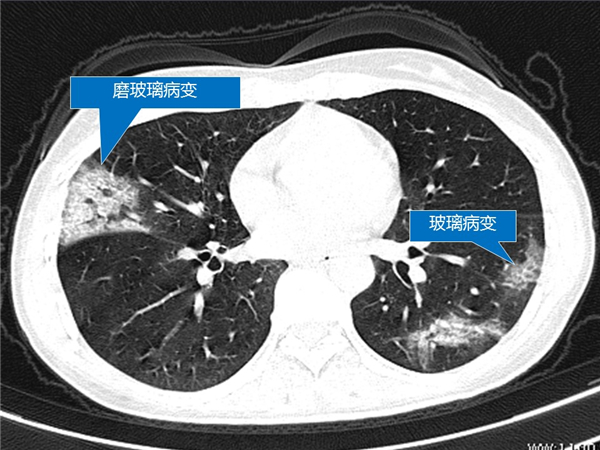

【病例分享】新型冠狀病毒感染肺部CT影像4例(常德市第一人民醫(yī)院)